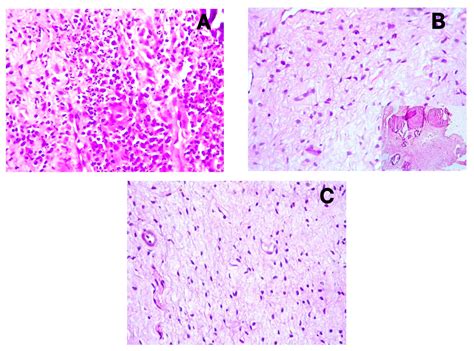

Irreversible Pulpitis Types

Chronic Hyperplastic Pulpitis

Pulp Polyp